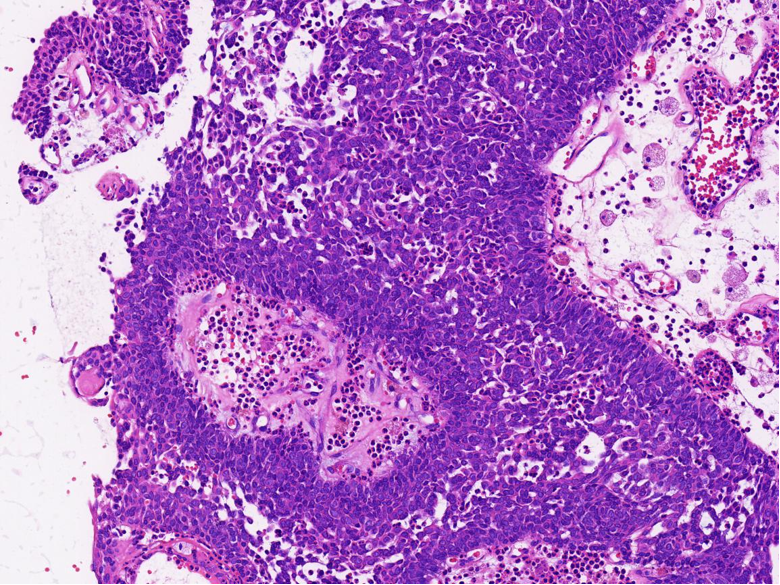

病理特征:宽薄乳头、 迷宫样内翻生长、单一肿瘤细胞形态、棘层松解、显著中性粒细胞浸润;

可见:细胞旋涡、透明细胞变、微囊形成、黏液纤毛上皮帽、部分肿瘤细胞异型性增加、坏死。

FISH检测显示患者肿瘤细胞核内红绿分离信号占比30%,结果阳性,提示DEK 基因发生断裂。

病理诊断:(左泪囊)DEK-AFF2 融合相关的鳞状细胞癌。